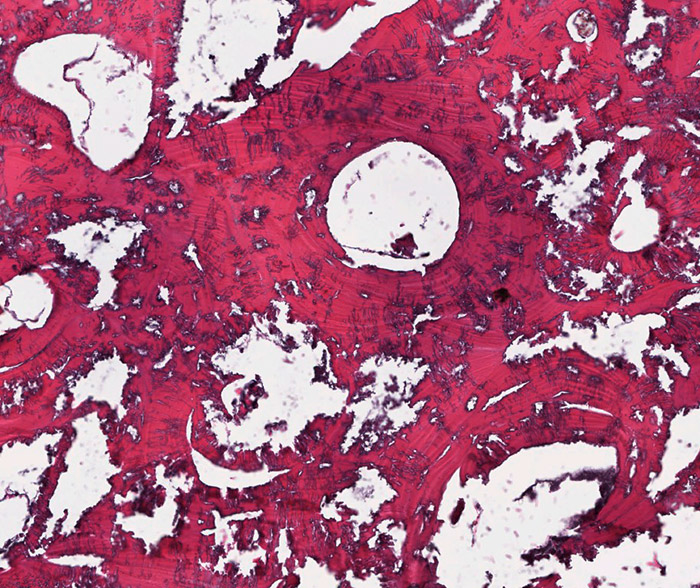

Figure 9

Paraffin embedding, haematoxylin and eosin, 40x. Sample taken out of the lesion.

The remains are well preserved. Morphological examination of skull and pelvis clearly classify the individual as female. The age at death was between 30 and 50 years. There is an intensely calcified bone proliferation at the right side of the os frontalis (fig. 2). Plain X-ray and CT imaging show a large (5.3 x 3 x 8.7 cm) sclerotic lesion in the area of the right temple with a partly bulging appearance (fig. 4). Figure 5 shows representative slices of the admission CT. A differentiation between tabula interna, diploë and tabula externa is not possible in major parts of the lesion. The inner boundary of the lesion shows multiple smooth-edged irregularities. There is a diffuse thickening of the right skull vault (right 7 mm, left 4 mm). The left skull vault presents a mix of sclerotic areas and areas with normal appearance with a clear differentiation between tabula interna, diploë and tabula externa. CT imaging and plain X-ray show a wedge-shaped area in the centre of the lesion that is filled with material of lower X-ray density than the adjacent bone (figs 5 and 6). Histology shows mature organised lamellar bone tissue with ordered formation of trabeculae (figs 7–9). No pathological alterations were found in the postcranial bones.

Histomorphological analysis revealed mature, structured lamellar bone without indication of an associated immature or fibrous component. The bone lesion is dense and without evidence of lytic areas. Although viable cellular components, which could have shown signs of nuclear atypia, could not be demonstrated, the mature architecture of the remnant bone structures do not raise the suspicion of malignancy.

Moreover, a reactive lesion like a callus formation as a result of trauma or osteomyelitis seems to be unlikely because of the orderly architecture and the purely lamellar matrix formation. The histological findings also exclude Paget’s disease or hyperparathyroidism [33, 34], since both conditions involve signs of heavy bone remodelling. Primary malignant conditions can be excluded owing to the macroscopic and microscopic findings. However, the macroscopic appearance could be consistent with osteoblastic metastases as well. Rather, the systematic arrangement of the lesions, their absence on the other bones (pelvis, femur) and the histology findings exclude this differential diagnosis.